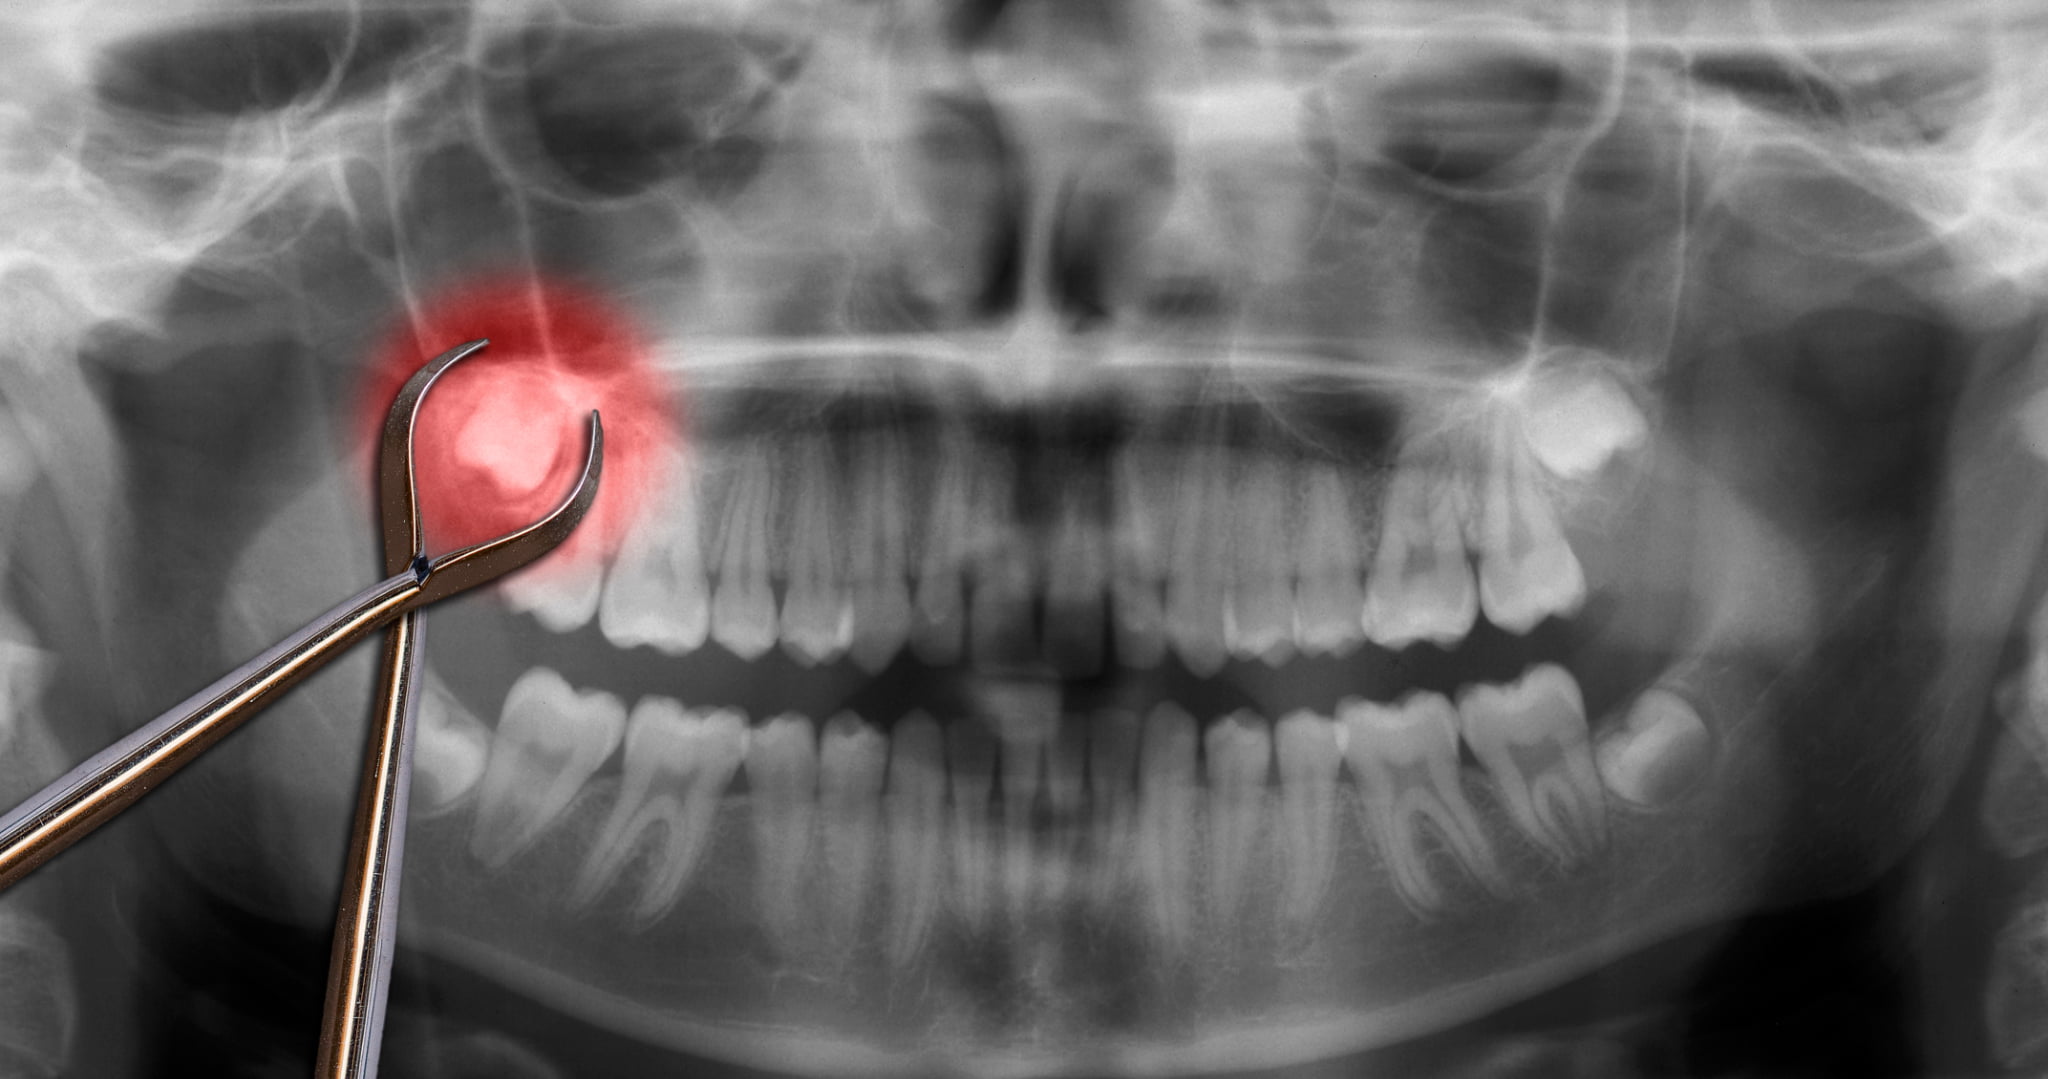

診察・レントゲン検査

まず歯科医院での診察と検査から始まります。目視だけでは歯の全体像を正確に把握できないため、レントゲンやCT検査で親知らずの位置、角度、神経との距離、骨の状態などを詳しく確認します。

これらの情報は、抜歯が必要かどうかを判断するために欠かせないものです。将来のトラブルを回避するためにも非常に重要といえます。

抜歯

処置の内容は、親知らずの埋まり方によって異なります。歯ぐきの下に完全に隠れている場合は、歯ぐきを切開して骨を少し削り、親知らずを分割して取り出すことが一般的です。歯の位置や形によっては、抜歯に30分〜1時間ほどかかることもあります。

処置中は麻酔が効いているため、痛みはほとんど感じませんが、圧迫感や引っ張られるような感覚があることもあります。処置後は傷口をしっかり縫合し、ガーゼを噛んで止血します。